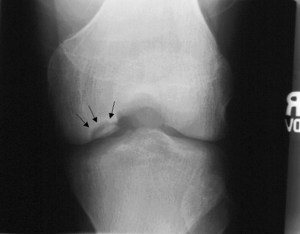

Osteochondritis dessicans (os-tee-o-kohn-DRY-tis DES-uh-kanz) is a joint condition in which a piece of cartilage, along with a thin layer of the bone beneath it, comes loose from the end of a bone. Caused by reduced blood flow to the end of a bone, osteochondritis dessicans occurs most often in young men, particularly after an injury to a joint. The knee is most commonly affected, although osteochondritis dessicans can occur in other joints, including your elbow, shoulder, hip and ankle. If the loosened piece of cartilage and bone stays put, lying close to where it detached, you may have few or no symptoms of osteochondritis dessicans, and the fracture can often heal by itself. Surgical repair may be necessary if the fragment gets jammed between the moving parts of your joint.

Throughout junior high I had been having left knee pain during athletics and activity, symptoms like locking up, throbbing sensations, sharp piercing pains. My father, being in the orthopedic sales business, knew all the best local orthopedic surgeons and in the fall of 1981 we finally decided to get into see someone and have some x-rays taken. OCD was the diagnosis. Of course at the time, that didn’t mean anything to any of us. Unfortunately, now I know the condition all too well. The treatment I was to choose from? Either knee surgery or a one year period of inactivity to try to allow the loose cartilage to reheal to the bone in my knee and hopefully fend off many future issues. As I was only 13 years old at the time the choice was clear, stay off the knee for a year and see what happens. This didn’t mean complete rest or crutches, just avoid sports for a year, no running around, no hard-pounding activities.

As promised, your blog’s amusing, energetic, and a general good morning read. (The x-ray is flipped, btw. Fibula goes on the other side on a right leg. That’s why the “R” marker shows backwards. I’m a rad tech.)

That’s funny, I’ve certainly seen enough of my own knee x-rays but would never have noticed this one being flipped! Thanks for visiting!